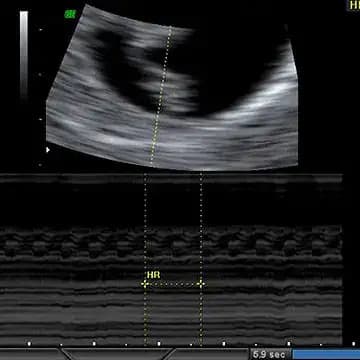

āĻā§āϰā§āύā§āϰ āĻŦā§āĻĄāĻŧā§ āĻāĻ āĻžāϰ āĻāĻ āĻāĻŦāĻŋāϤ⧠āĻāĻĒāύāĻŋ āĻĒā§āϰāĻĨāĻŽ āĻā§āϰāĻžāĻāĻŽā§āϏā§āĻāĻžāϰā§āϰ āĻāĻā§āϰ āϏāĻĒā§āϤāĻžāĻšā§āϰ āϤā§āϞāύāĻžāϝāĻŧ āĻŦā§āĻļ āĻŦāĻĄāĻŧ āϧāϰāύā§āϰ āĻĒāϰāĻŋāĻŦāϰā§āϤāύ āϞāĻā§āώā§āϝ āĻāϰāĻŦā§āύāĨ¤āĻļāĻŋāĻļā§āϰ āĻĻā§āĻšā§āϰ āĻŽāĻžāĻāĻāĻžāύ⧠āĻāĻŽā§āĻŦāĻŋāϞāĻŋāĻāĻžāϞ āĻāϰā§āĻĄ āϰāϝāĻŧā§āĻā§ āĻāĻŦāĻ āϏ⧠āĻāĻŋāϤāϰ āĻĻāĻŋāĻā§ āĻā§āĻāĻā§ āĻšāϝāĻŧā§ āĻāĻā§āĨ¤āĻāĻŦāĻŋāϰ āĻĄāĻžāύ āĻĻāĻŋāĻā§ āĻāĻĒāϰ⧠āĻŽāĻžāĻĨāĻž āĻĻā§āĻāĻž āϝāĻžāĻā§āĻā§āĨ¤āĻā§āĻ āĻā§āĻ āĻā§āĻāĻĄāĻŧāĻŋ āĻĻā§āĻāĻž āϝāĻžāĻā§āĻā§,āϝā§āĻāĻžāύ⧠āĻšāĻžāϤ āĻĒāĻž āĻā§āϰāĻŽāĻļ āĻŦā§āĻĄāĻŧā§ āĻāĻ āĻŦā§āĨ¤